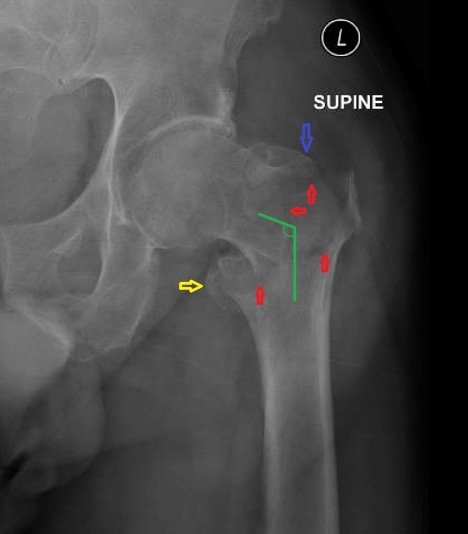

Plain film of the left hip showed acute comminuted displaced intertrochanteric fracture (red arrows) of left femur with varus angulation (green lines) and no dislocation. Greater (blue arrow) and lesser (yellow arrow) trochanters are annotated for reference.